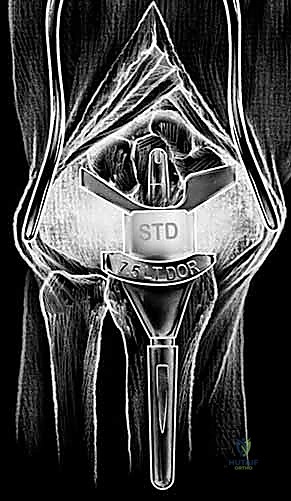

Carpal preparation requires exacting precision. Using the Maestro system as the archetype, the carpal resection guide is positioned to allow resection of 2 to 3 mm of the capitate head. It is provisionally held in position with two 0.062-inch Kirschner wires. The first wire is placed into the capitate neck and the second into the metaphysis of the third metacarpal, ensuring that the guide is perfectly parallel to the third metacarpal axis. With proper placement, the ulnar guide wing will lie close to the triquetrum–hamate articulation, and the radial wing will bisect the scaphoid at its distal third.

With the wrist held in neutral, the radius is scored through the cutting slot in the guide to provide a reference for the distal radial resection. The thumbscrew on the carpal resection guide is loosened to allow insertion of the radial resection guide boom. Following radial resection, the scaphoid, capitate head, hamate edge, and triquetrum are resected at a precise 90-degree angle to the axis of the forearm jig. The trial carpal plate is provisionally determined by the curvature and width of the remaining proximal carpal surface; it must lie flush with the hamate and proximal capitate surfaces. Unlike older designs, it is not always necessary to attempt fusion of the distal pole of the scaphoid to the surrounding carpus. The Maestro Wrist has a provision to replace the entire scaphoid using a carpal plate incorporating a modular radial augment, of which three separate sizes are available.

Following capitate reaming, the chosen carpal plate and stem are assembled and inserted into the capitate and seated onto the resected carpal surface. The carpal plate is anchored to the carpus with a radial screw that optimally does not penetrate the second metacarpal, and a second screw placed ulnarly into the hamate. This construct ensures stable distal fixation while avoiding the deleterious lever arm of a long metacarpal stem. Trial reductions are performed to assess stability, range of motion, and impingement. Once kinematics are confirmed, the definitive ultra-high-molecular-weight polyethylene (UHMWPE) body—which is direct compression molded onto a cobalt chrome alloy radial body—is impacted. The capsule and extensor retinaculum are meticulously repaired to prevent extensor tendon bowstringing and provide a robust soft tissue envelope over the implant.